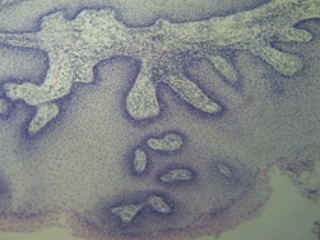

Частный владелец, проживающий г. Краснодар доставил новообразование собаки(возраст 5,5 лет). Читать далее..